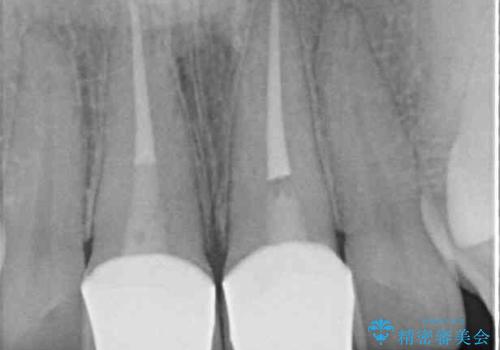

補綴治療に先立ち、歯の形態を修正する必要があったため、残念ではありますが根管治療を行うこととしました。

1度の来院で進められる限りの処置を行ったため、4回の来院で僅か1ヶ月で治療を終えることができました。

気になっていた前歯の問題が解決し、患者様には大変満足していただきました。